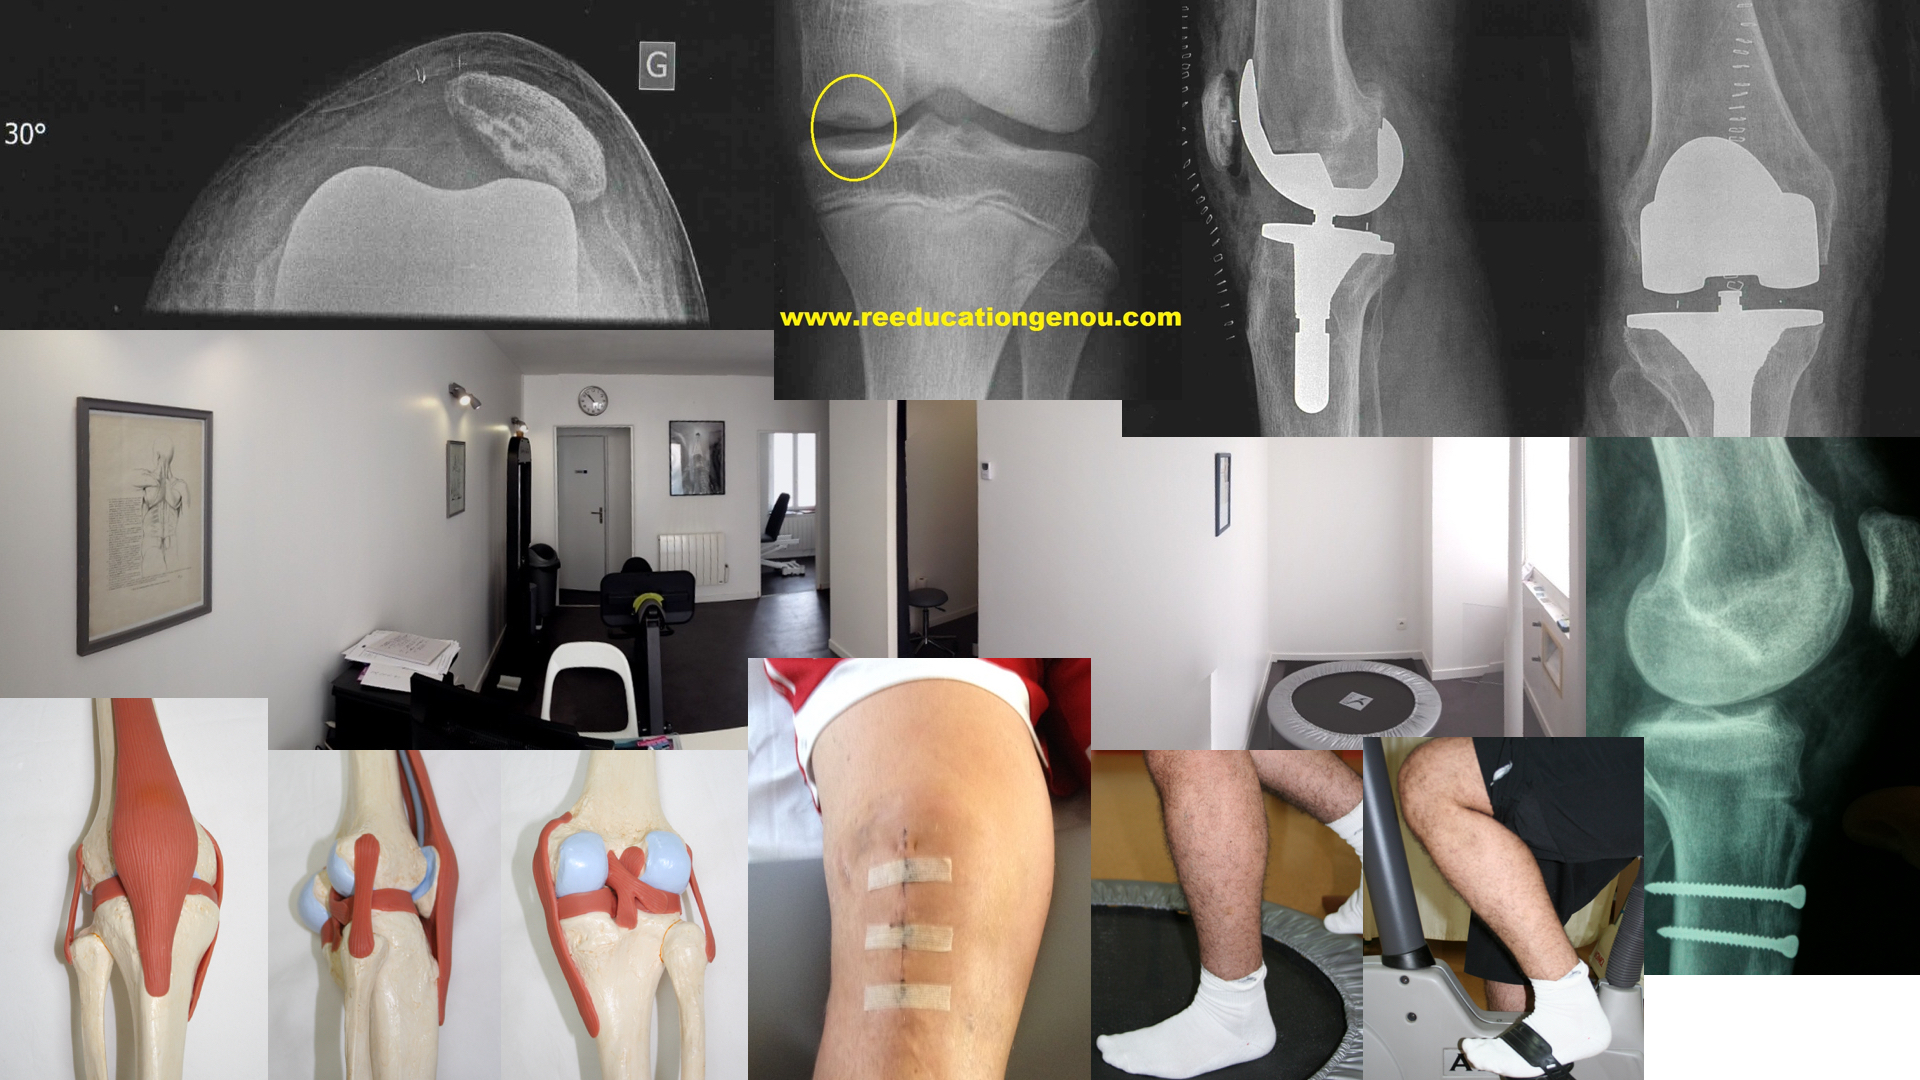

Rotule dysplasique ! C'est quoi ?

Dysplasie ?

La rotule est posée sur le fémur. A chaque mouvement de flexion extension du genou la rotule se déplace en glissant sur le bas du fémur. Cette surface est recouverte de cartilage et se nomme la trochlée

Parfois cette articulation est mal configurée : trop plate. on parle de trochlée plate c'est une des nombreuses dysplasies (angle d'ouverture supérieur à 140°)

Dans de rares cas extrêmes la trochlée n'est plus creusée mais "convexe" (grade B et D de la classification de D. Dejour) avec des conséquences mécaniques. Dans ce cas lors de la flexion la rotule ne s'engage pas mais glisse sur le coté latéral avec parfois un bruit voire un ressaut visible : c'est le bump ou le J-signC'est le SEUL cas (la forte dysplasie) de rotule douloureuse qui peut être chirurgical après un long bilan radio + scanner TA-GT et plusieurs avis de chirurgiens.

une rotule normale face à sa trochlée

TA-GT du genou gauche

ici elle est normale car inférieure à 20mm

sacrée dysplasie sur une ado de 17 ans qui vient après une 1ère luxation de la rotule!